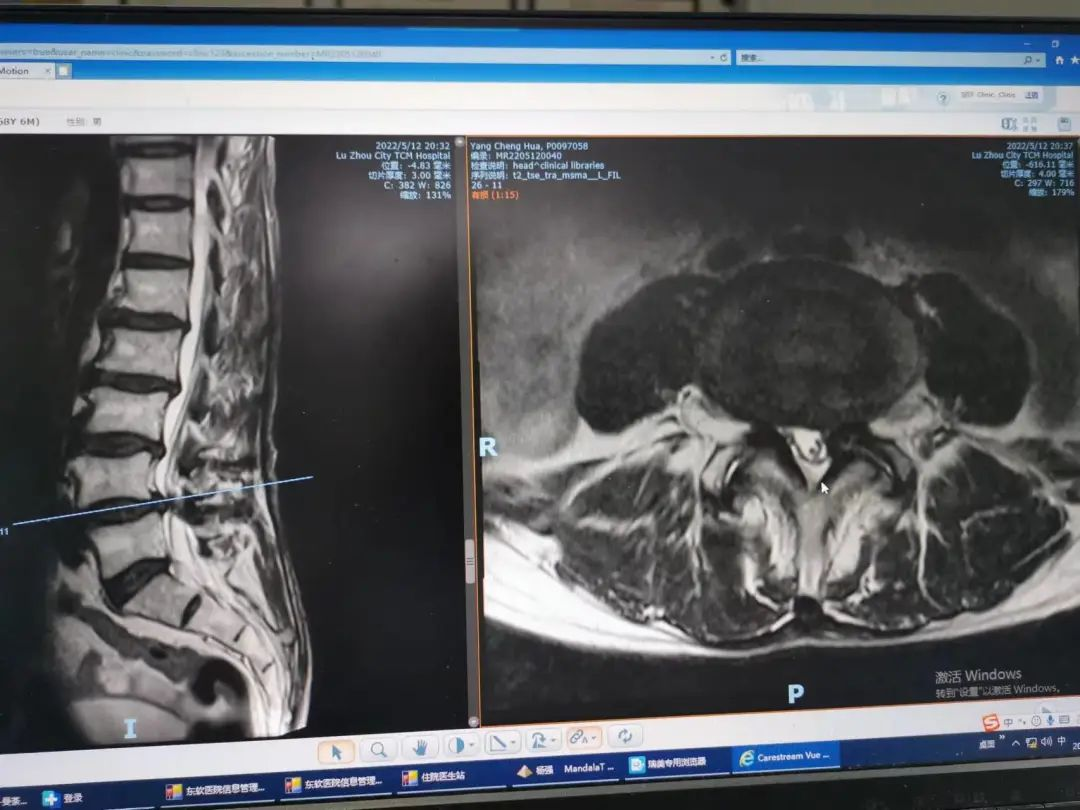

杨先生腰椎管狭窄症拍片

原来,杨先生无明显诱因的出现颈肩部、腰部疼痛,在当地医院住院治疗后症状稍缓解,随后疼痛症状又加重,并反复发作。近日,杨先生状况已是下地行走困难,还伴四肢疼痛、麻木、无力等,为求进一步治疗,杨先生来到泸州市中医医院就诊。经检查,杨先生是患了脊髓性颈椎病加腰椎管狭窄症

腰椎椎管狭窄症是指各种原因引起椎管各径线缩短,压迫硬膜囊、脊髓或神经根,从而导致相应神经功能障碍的一类疾病。此病多发于40岁以上的中年人。静或休息时常无症状,行走一段距离后出现下肢痛、麻木、无力等症状,需蹲下或坐下休息一段时间后,方能继续行走。随着病情加重,行走的距离越来越短,需休息的时间越来越长。